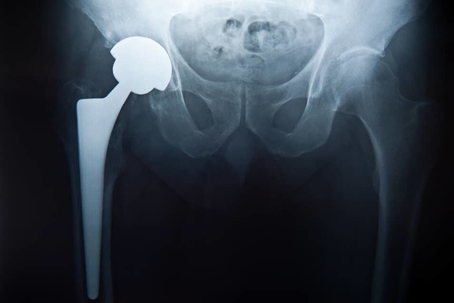

an x-ray of a hip replacement

Hip replacement procedures are common and help many patients regain their mobility and increase their quality of life.

Like any medical procedure, however, there is a risk of complication.